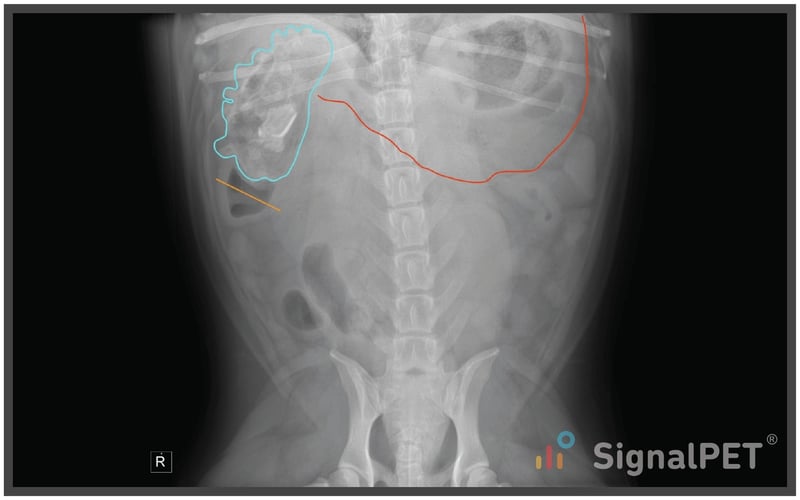

From landing.signalpet.com

Radiology Case of the Week Canine Gastrointestinal Foreign Body Dog Duodenum Obstruction What causes intestinal blockage in dogs? A bowel obstruction is a complete or partial blockage in the stomach or intestines, which prevents solids or liquids from passing through. Obstruction is most common and is due to the dog’s inability to pass poorly digestible, often firm matter (such as hair or bones) that has become mixed with fecal material. The dilated. Dog Duodenum Obstruction.